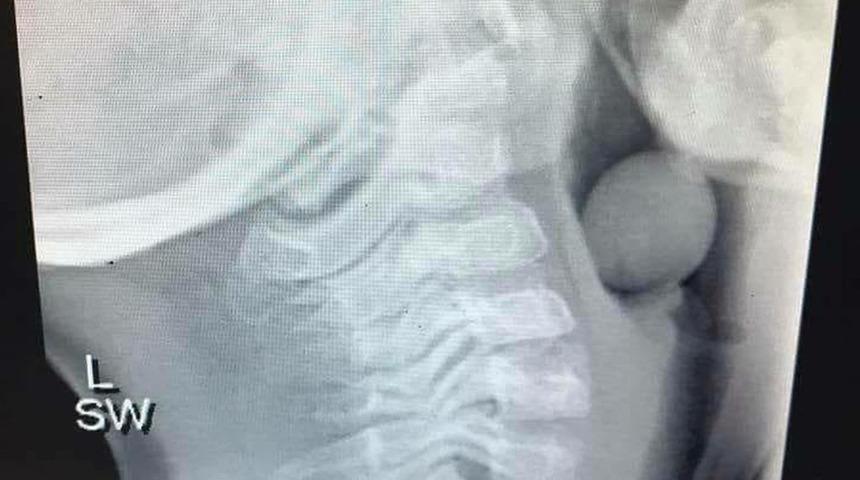

Klinisyen anne Angela Henderson, beş yaşındaki çocuğunun solunum yoluna kaçan üzümün röntgenini paylaştı. Genel anesteziyle ameliyat edilen küçük çocuk hava yolunun bir kısmının açık olması sayesinde ölümden döndü.

Çocukların oyun oynamak için acele ettiklerini bu neden yiyeceklerini tam çiğnemediklerini de, söyleyen Henderson ebeveynlerin her zaman boğulma tehlikelerine karşı uyanık olmaları gerektiğini bir kez daha sözlerine ekledi.

Yedi yaşın altındaki çocuklarda üzümlerden boğulma gerçekten çok yüksek olduğu için, bu gibi yiyeceklerin düzgün bir şekilde kesilmesi gerekiyor.

Üzümler, gıdayla ilişkili boğulma olaylarında ölen çocuklar arasında en yaygın üçüncü ölüm sebebi.